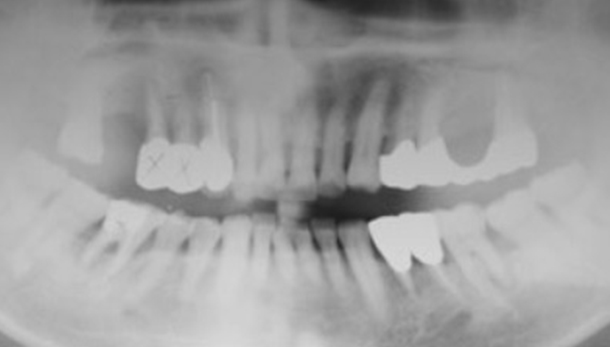

Combined Gbr

| patient information | |

|---|---|

| age | 59 |

| gender | Old Male |

| implant |

#14, 16 : GBR → SST implants placement #46 : SST implants placement #26, 27 : sinus graft + simulaneous SST implants placement #36 : immediate SST implants placement + GBR |

Internal Hex Fixture : SST Type